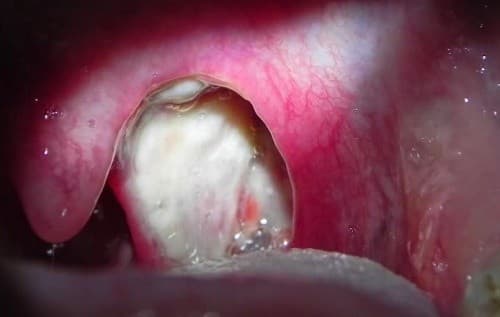

Amidan hốc mủ là tình trạng viêm nhiễm mạn tính. Do bề mặt của amidan không nhẵn mà có các hốc nên khi bị viêm nhiễm, vi khuẩn có thể ẩn náu lâu ngày trong hốc amidan mà gây viêm cục bộ một số hốc. Trong trường hợp này, lúc há miệng to soi vào gương, có thể thấy những chấm mủ trắng trên bề mặt amidan. Mủ đọng lâu ngày trong hốc amidan vón lại thành kén rồi do hoạt động của các cơ họng khi nuốt cùng sự cọ xát của thức ăn đi qua, các kén mủ trong hốc amidan bật ra (có mùi hôi).